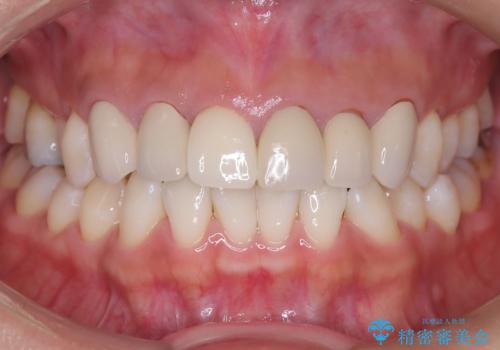

繰り返すプラスチックの欠けを解消。広範囲の修復に適したセラミッククラウン

担当医 河口智英